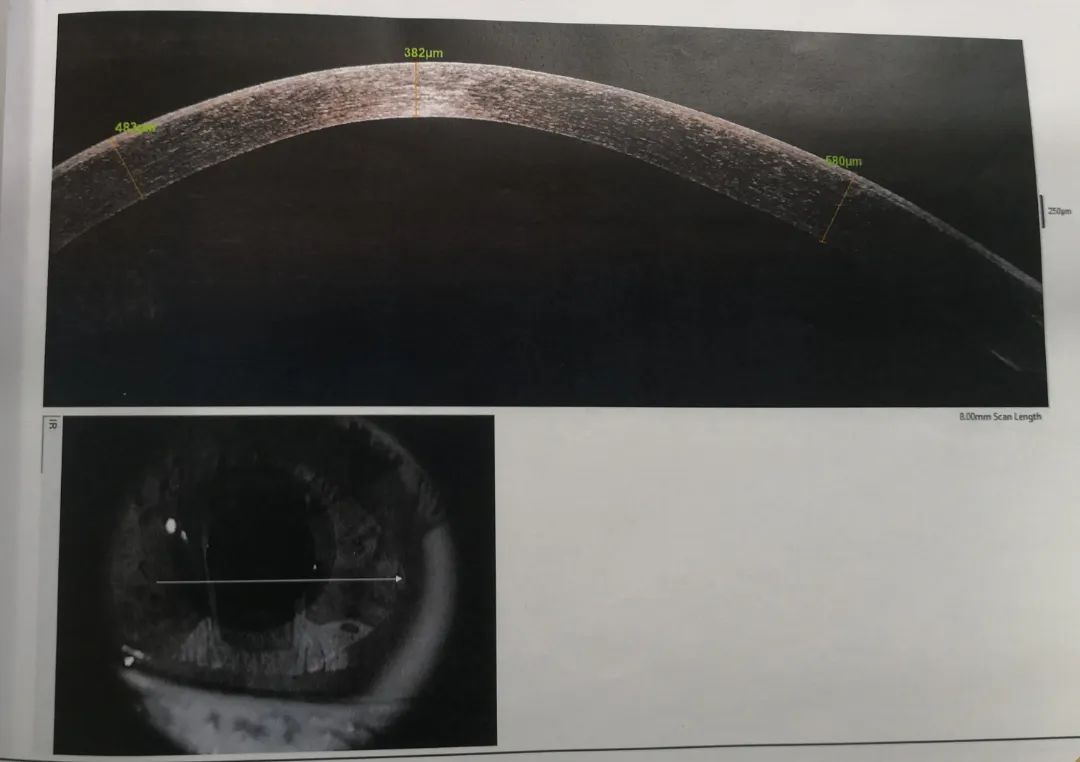

小雨重新回憶起之前的診治經(jīng)歷,確定此前的檢查中并沒有圓錐角膜的檢查,羅順榮副主任為她完善了相關(guān)檢查。檢查結(jié)果顯示,小雨左眼還是圓錐角膜初期,但右眼已經(jīng)是圓錐角膜的完成期,左眼角膜厚度為489μm,而右眼僅剩下382μm。

治療刻不容緩,羅順榮副主任建議小雨馬上進(jìn)行角膜交聯(lián)的手術(shù),通過手術(shù),增加角膜的強(qiáng)度,阻止圓錐角膜進(jìn)一步發(fā)展。